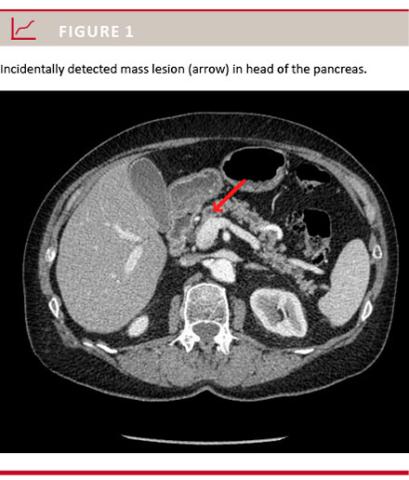

Patients referred to our department for EUS between September 2012 and September 2013 because of an incidental finding in the pancreas/distal bile duct noted at a CT were prospectively enrolled in the study. An incidental finding was defined as a potentially pathological condition that had no relation to the reason for performing the CT; for example the finding of a 2-cm mass lesion in the head of the pancreas in a patient for whom the indication for CT was constipation was considered an incidental finding (Figure 1). CT scans had been performed either at local hospitals or at our own department of radiology; but before deciding on an EUS, each patient had their CT re-evaluated at a multidisciplinary team conference including radiologists with a special interest in CT and gastro-intestinal diseases and the surgeons who would later perform the EUS, if decided. Thus, only those patients for whom EUS was chosen as the best procedure for further diagnostic work-up after the re-evaluation of the CT were eligible for the study.